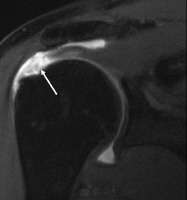

Diagnostic modalities, dependent on circumstances, include X-ray, MRI, MR arthrography, double-contrast arthrography, and ultrasound. Although MR arthrography is currently considered the gold standard, ultrasound may be most cost-effective.[16] Usually, a tear will be undetected by X-ray, although bone spurs, which can impinge upon the rotator cuff tendons, may be visible.[17] Such spurs suggest chronic severe rotator cuff disease. Double-contrast arthrography involves injecting contrast dye into the shoulder joint to detect leakage out of the injured rotator cuff[18] and its value is influenced by the experience of the operator. The most common diagnostic tool is magnetic resonance imaging (MRI), which can sometimes indicate the size of the tear, as well as its location within the tendon. Furthermore, MRI enables the detection or exclusion of complete rotator cuff tears with reasonable accuracy and is also suitable to diagnose other pathologies of the shoulder joint.[19]

MRI

Magnetic resonance imaging (MRI) and ultrasound[27] are comparable in efficacy and helpful in diagnosis although both have a false positive rate of 15 - 20%.[28] MRI can reliably detect most full-thickness tears although very small pinpoint tears may be missed. In such situations, an MRI combined with an injection of contrast material, an MR-arthrogram, may help to confirm the diagnosis. It should be realized that a normal MRI cannot fully rule out a small tear (a false negative) while partial-thickness tears are not as reliably detected.[29] While MRI is sensitive in identifying tendon degeneration (tendinopathy), it may not reliably distinguish between a degenerative tendon and a partially torn tendon. Again, magnetic resonance arthrography can improve the differentiation.[29] An overall sensitivity of 91% (9% false negative rate) has been reported indicating that magnetic resonance arthrography is reliable in the detection of partial-thickness rotator cuff tears.[29] However, its routine use is not advised, since it involves entering the joint with a needle with potential risk of infection. Consequently, the test is reserved for cases in which the diagnosis remains unclear.